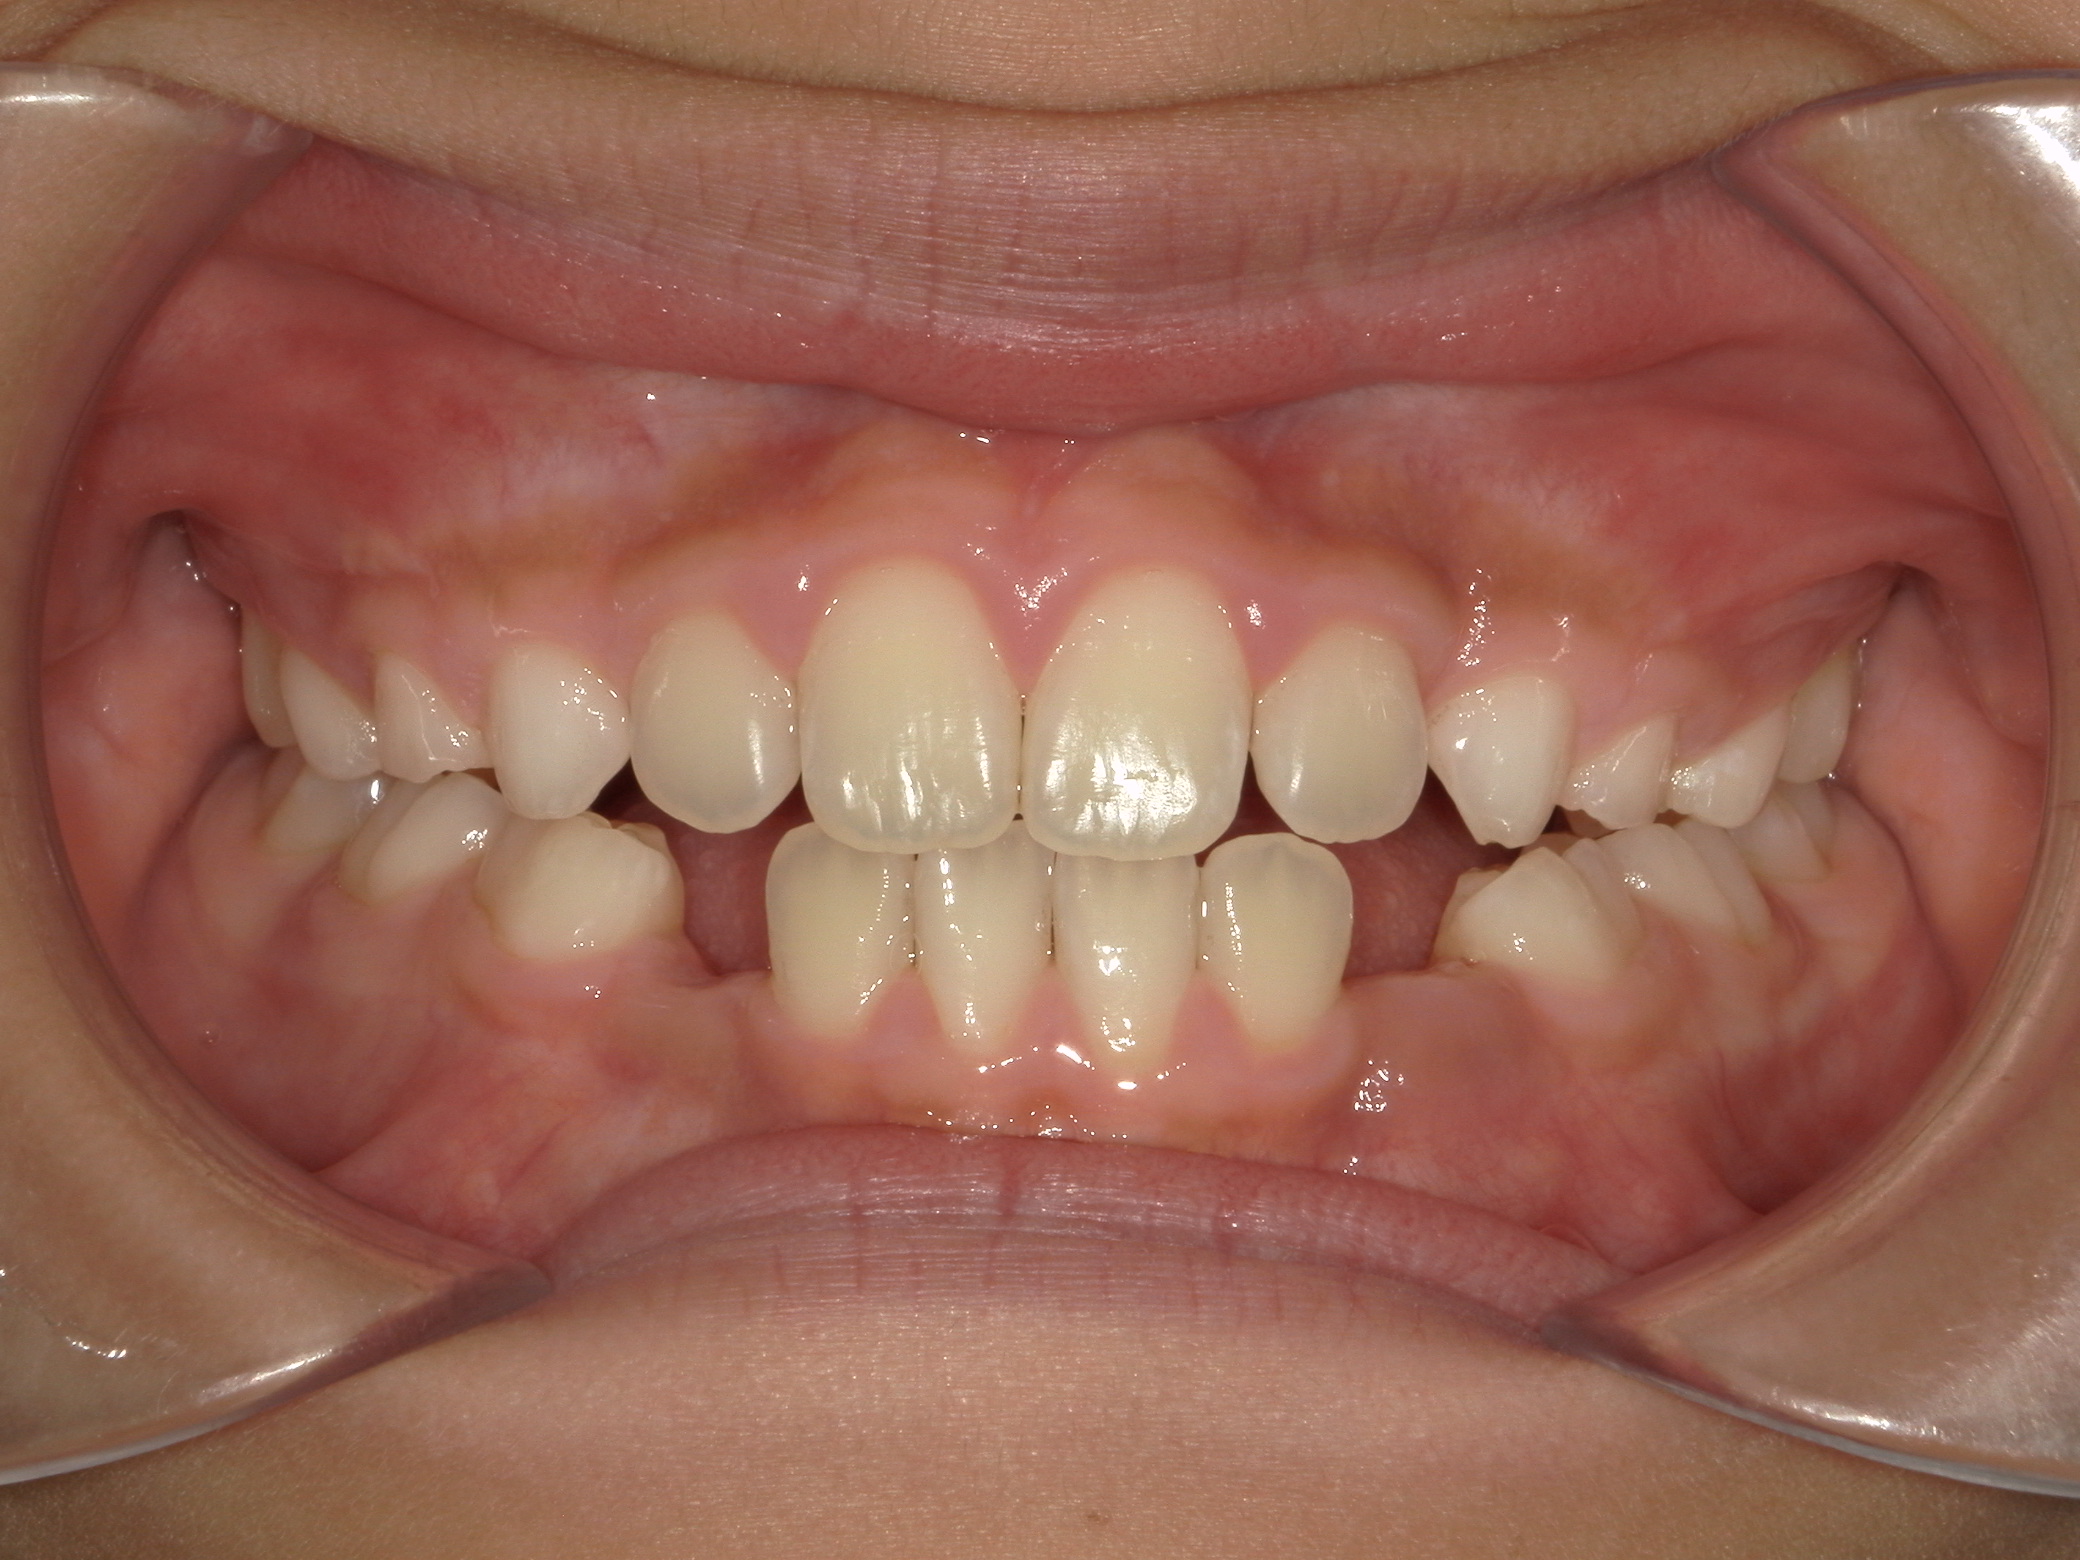

歯の位置異常(犬歯位置異常)

8歳 男性

治療例前

歯列弓拡大、前歯の正常被蓋獲得、犬歯の誘導

拡大床、部分ワイヤー

495,000円(税込)

2年6か月

左上犬歯の位置異常が初診時検査で認められました。外科的誘導は行っておらず、歯列弓をしっかり拡大し、乳歯を意図的に抜歯してあげることで本来の位置へ誘導することに成功しています。矯正歯科医院での適切な判断で外科処置を回避できた症例です。

2期治療にて仕上げの矯正治療を行う予定です。